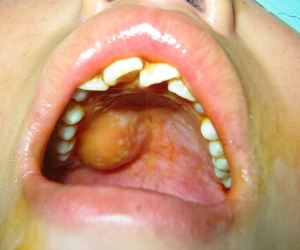

臨床表現

牙源性腫瘤種類繁多,可以發生了任何年齡。大部分發生在上頜骨、下頜骨的骨組織內;也有的發生於牙齒臨近的牙齦、黏膜,被稱為外周型牙源性腫瘤。牙源性良性腫瘤的臨床表現多數為上頜骨或下頜骨膨隆,緩慢生長,無痛或輕微疼痛。牙源性惡性腫瘤的最常見的症狀是疼痛,快速生長、膨隆,腫瘤可侵蝕或穿透頜骨的骨皮質。